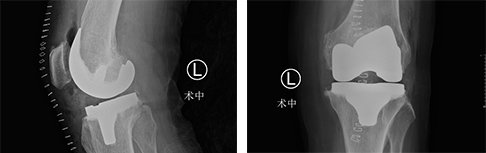

为了让吴奶奶安全顺利的完成手术,郝亮主任带领手术团队在Mako智能机器人的辅助下,为吴奶奶进行了膝关节置换术。在Mako机器人的辅助下,手术中对于截骨、假体安装等重要环节都进行了全程三维定位,并实时将角度、大小、骨质覆盖等重要信息通过数字影像及时传达给手术医生,帮助医生做出准确判断,这种客观数据的评判标准与传统手术只能凭借医生“自主认为”的方式相比,无疑更加精准、更加科学,这对患者术后的康复来说也大有益处。

经过团队成员的努力,吴奶奶的手术很成功,术后第二天就可以下床活动。